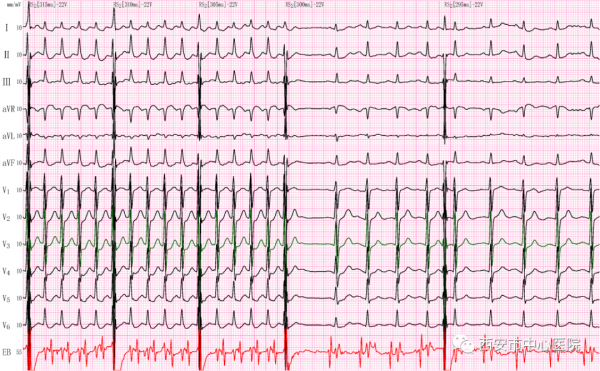

我們給患者插入食道電極,僅用數個脈衝(食道調搏治療)就終止了困擾患者二天多的心動過速。(圖1)

(圖1)

首先,從莫女士的鼻腔插入食道電極導管到達心臟位置,接入相應的導聯,記錄到如圖2所示的體表心電圖和食道心電圖(圖中紅色部分)。透過食道心電圖高大清晰的P波以及心房和心室的關係,我們可以明確莫女士的心動過速是因為心臟除了心房心室之間的正常的傳導通路(房室結)外,在心臟左側壁比別人多了一條“電路”(隱匿性旁路),如同我們生活中私接亂拉了一路電線,就是這條多餘的“電路”引起患者心跳增快,心慌、胸悶不適。莫女士的心律失常是“順向型房室折返性心動過速”。

(圖2)